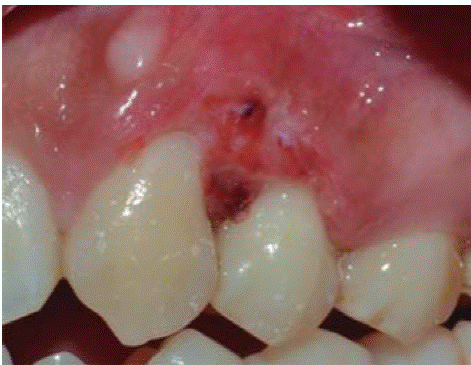

Tratamiento: primera sesión de instrucción de higiene oral seguido de biopsia excisional de lesión y gingivoplastia (Figuras 11 y 12).

Examen histopatologico: muestra constituida por epitelio acantósico, que muestra hiperplasia pseudoepiteliomatosa, lámina propia, canales vasculares tapizados de células endoteliales, infiltrado inflamatorio compuesto por linfocitos, células plasmáticas, histiocitos y ocasionales polimorfos nucleares. Estos hallazgos confirmaron el diagnóstico clínico (Figuras 13 y 14).

Figuras 13 y 14. (HE 5x) Epitelio acantósico, hiperplasia pseudoepiteliomatosa, lámina propia, aparentemente canales vasculares e infiltrado inflamatorio. (HE 10x) Canales vasculares tapizados de células endoteliales, infiltrado inflamatorio compuesto por linfocitos, células plasmáticas, histiocitos y ocasionales polimorfos nucleares.